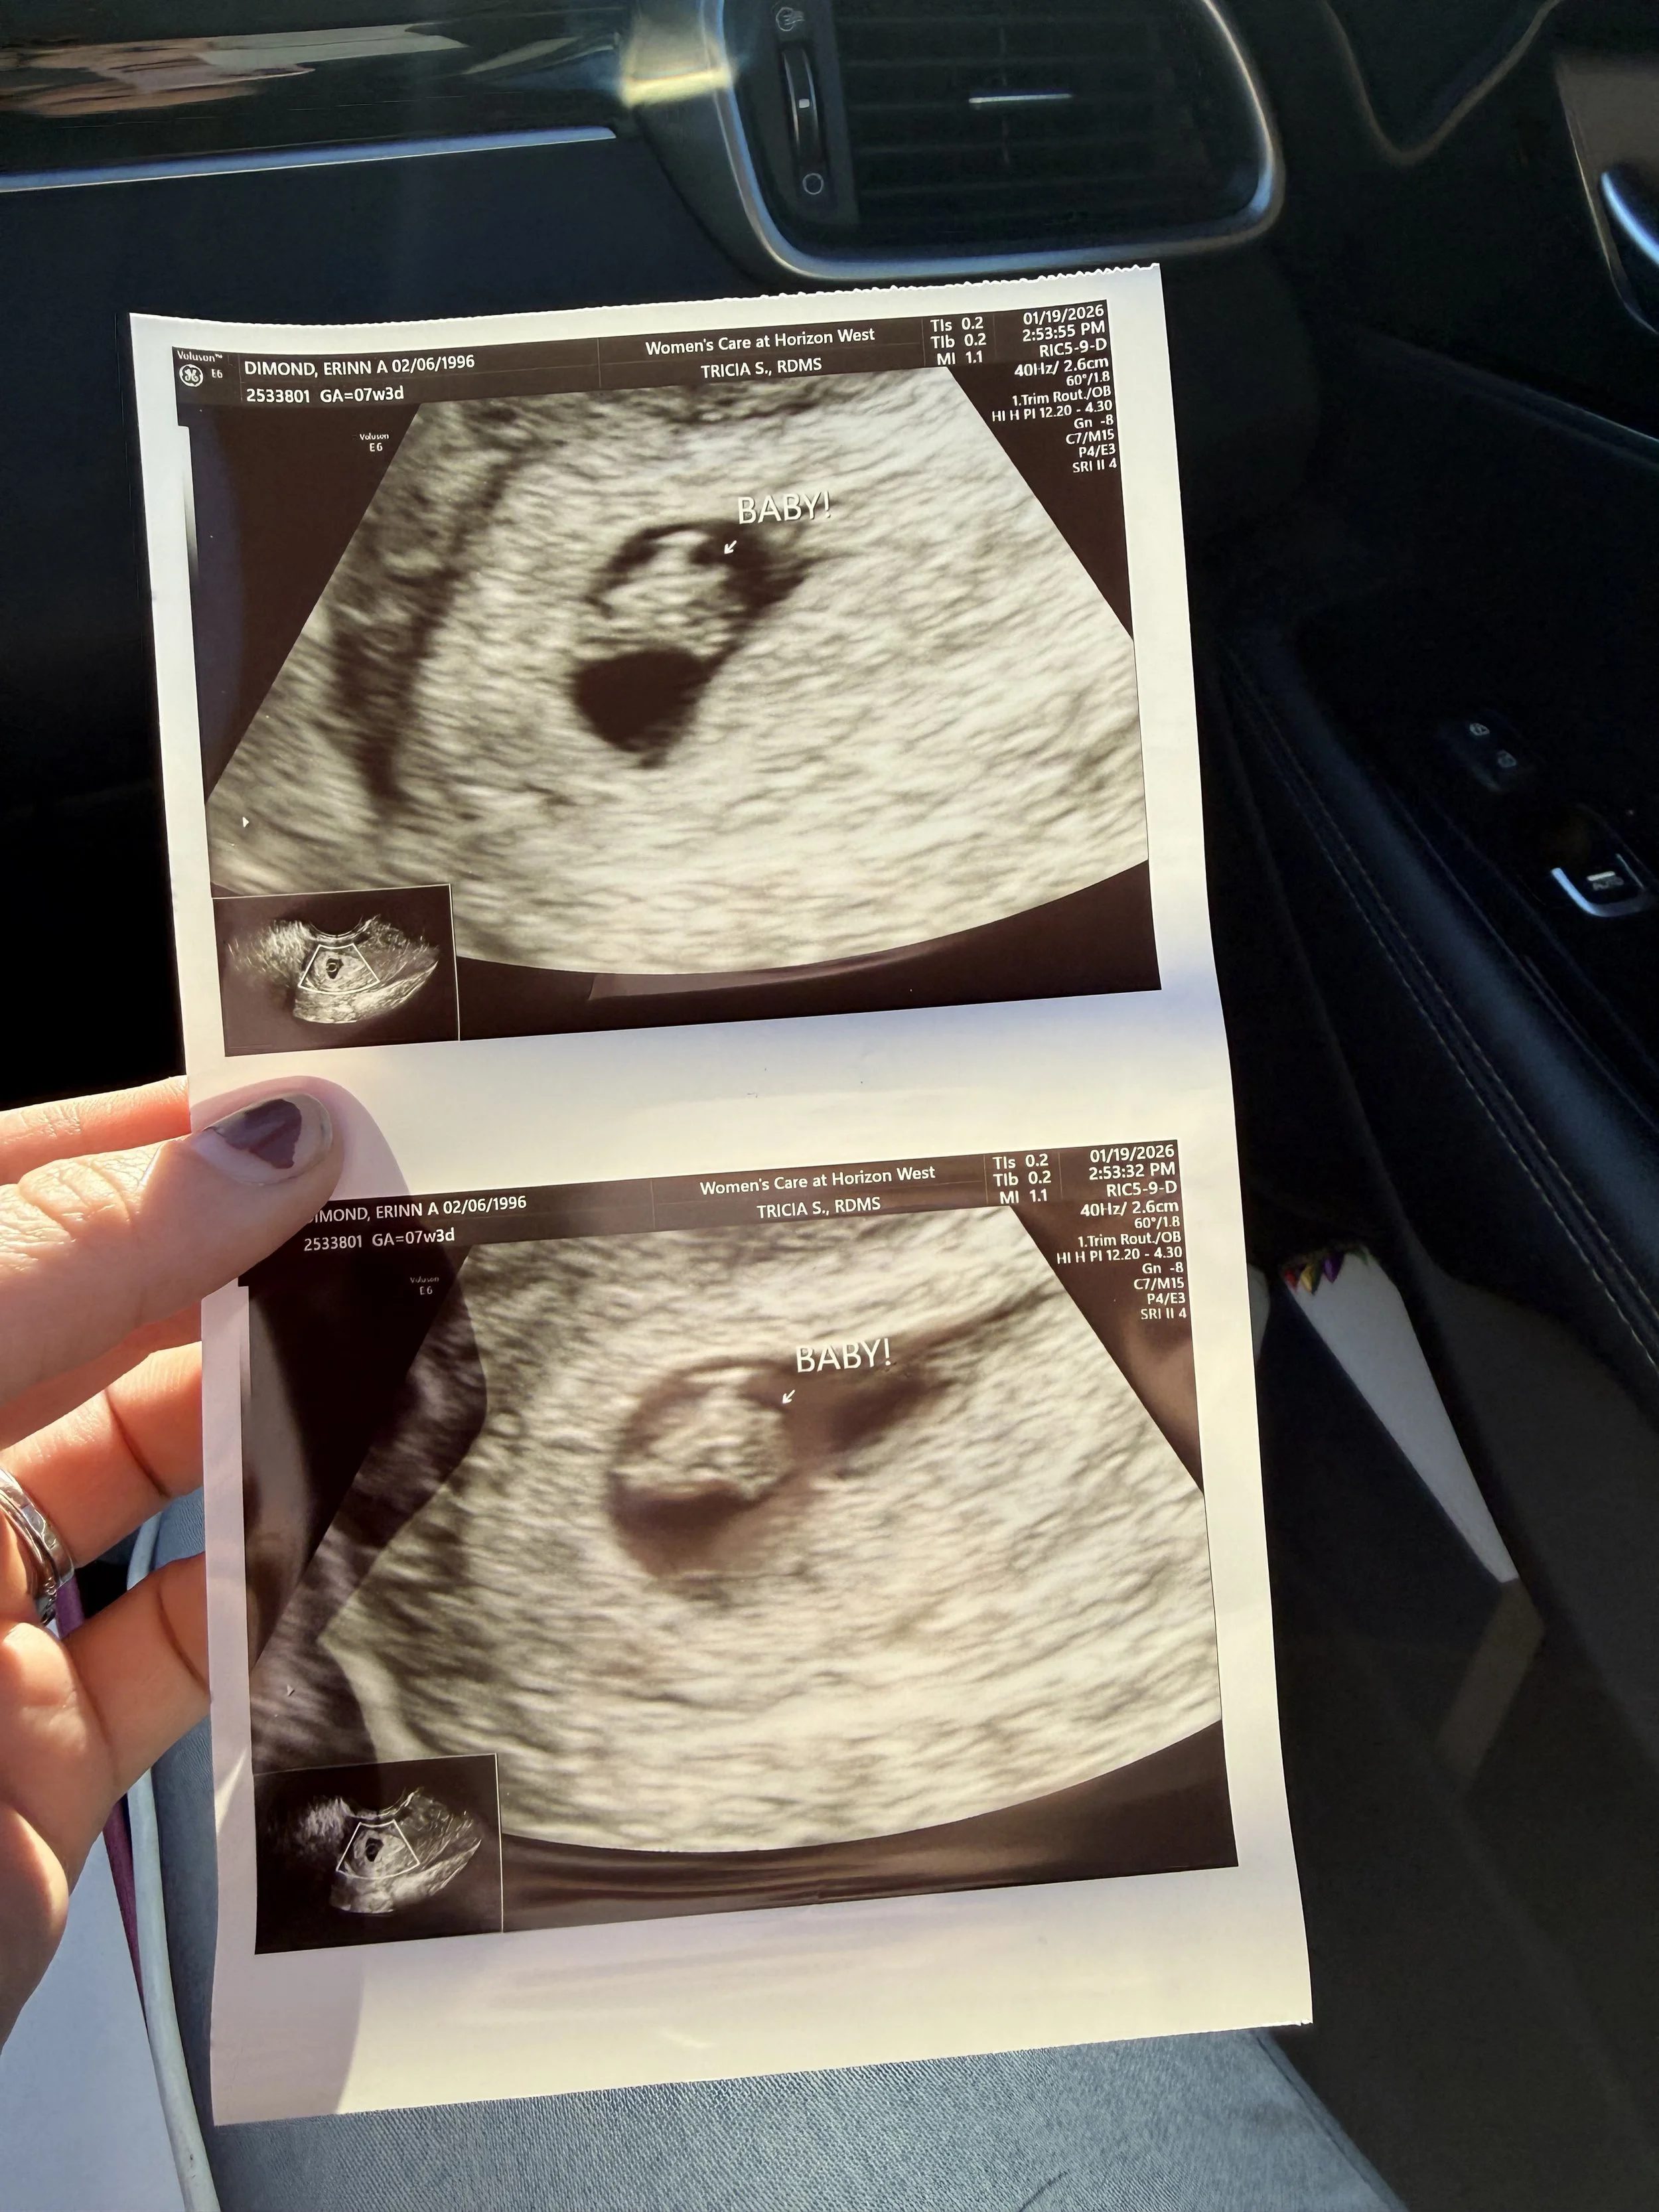

Yesterday, I turned thirty years old. Twelve days before that, my first baby died in my womb and I began to miscarry. I was eight weeks and two days pregnant.

Within a month we went from wishing for a Christmas miracle, to witnessing that miracle’s heart beating on the ultrasound screen, to mourning the death of someone we barely knew but loved so, so much. And now, all I have left is a box - a wooden keepsake box containing the ultrasound picture, the pregnancy test, my ER bracelet and paperwork, and a onesie we had bought especially for this baby - and a faux-sapphire ring I bought off of eBay (sapphire would have been the baby’s birthstone if we had made it to term) that sits on my right hand.

When I went in for my first ultrasound at seven weeks pregnant, the tech found that the baby was measuring a week small. A couple of blood tests revealed that my progesterone was dangerously low. I was given a progesterone supplement prescription, but by the time I started taking the pills it was too late.

It’s fair to assume that my progesterone was low the whole time I was pregnant, and that the lack of this vital hormone could be what caused my baby to die. After the OB confirmed that I had miscarried, she told me to let her know as soon as I find out I’m pregnant again. “We’ll get you in ASAP, we’ll test your hormones, and we’ll get you on supplements if any are low,” she said. “We’ll give the next baby the best chance we can.”